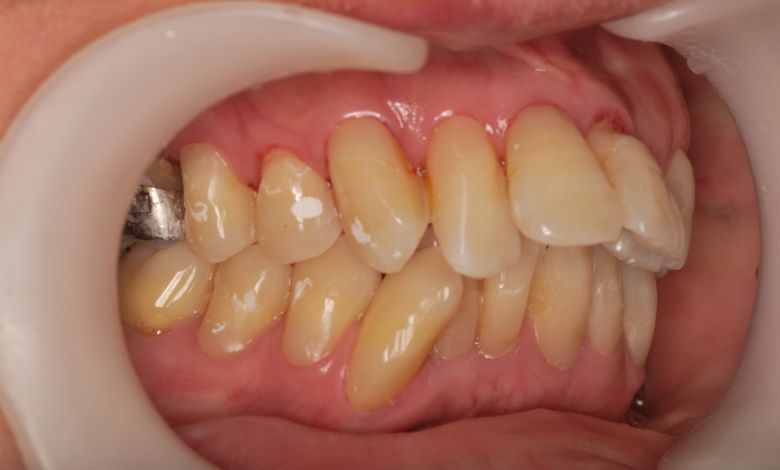

上下顎ともに犬歯が唇側に大きく突出しており、歯列弓が狭小なため、

他院では上下左右4本の便宜抜歯を前提とした矯正治療を提案されていました。

上顎には左右の犬歯が著しく唇側に偏位している

精密検査の結果、当院では抜歯を行わず、歯列弓の拡大によってスペースを確保し、非抜歯での矯正治療を選択しました。歯列の叢生(ガタガタ)は解消され、機能的かつ審美的に優れた咬合が得られました。